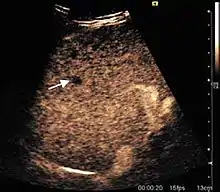

Hepatic hemangioma (2D). The lesion is located in the left hepatic lobe. Note precise delineation, their increased echogenity and the heterogeneous internal structure.